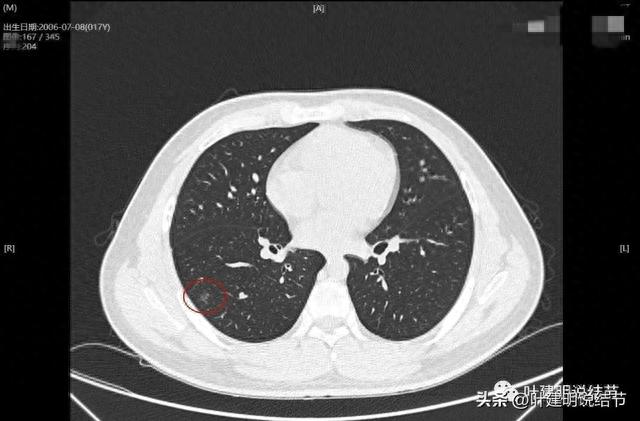

先看2023年7月的:

病灶出現

輪廓較清,密度不是很純

有微小血管進入

血管貼邊走行以及發出細小血管進入病灶。灶內有點狀偏高密度。

微小血管進入,病灶表面不平,也不光滑,內部密度不均。

邊緣顯得有點毛糙

邊緣部分也有另外方向的血管也發出分支進入病灶

右肺下葉混合磨玻璃結節或異質性磨玻璃結節,整體輪廓較清,瘤肺邊界清楚便邊緣毛糙;有多支微小血管進入;灶內密度不均,有點狀偏高密度。此灶如果持續存在,則基本上要考慮腫瘤范疇的,從密度來看,像原位癌些,但有微血管進入與點狀偏高密度,所以要加一級,微浸潤性腺癌不能除外。當然如果首次發現,可考慮先口服消炎治療10-12天,過4個月左右復查再看。